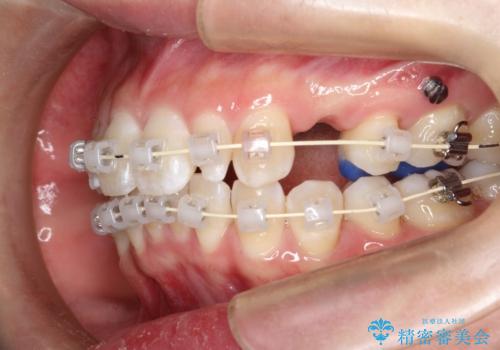

- 矯正装置

- 審美装置

- 治療期間

- 2年1ヶ月

- 治療回数

- 10-30回